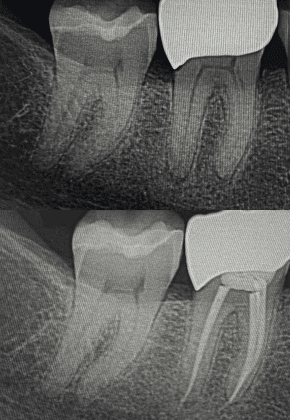

My mission is to offer excellence for you and your family, combining care, technology, and a truly human touch. I believe in individualized treatment, where each patient is unique and their needs are the priority. With an integrative approach, we look beyond the teeth to care for your overall health and well-being.